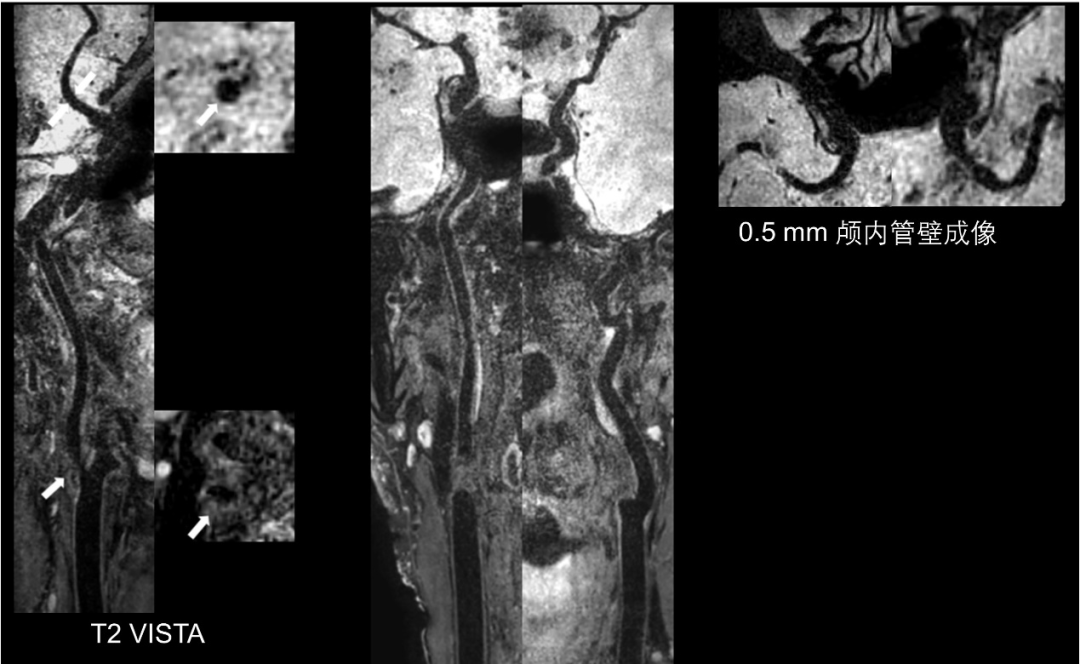

1、实现了颅内动脉快速高分辨率MR管壁成像;

本研究序列调测的所有磁共振实验均在清华大学生物医学影像中心的一台3.0T磁共振扫描仪(Ingenia, Philips Healthcare, The Netherlands)上进行,使用配套的32通道头线圈及8通道颈动脉线圈进行成像。颅内外大范围动脉管壁T1及T2加权成像均采用黑血快速自旋回波成像(Turbo Spin-Echo, TSE)序列实现,成像范围包含大脑中动脉及全部颈动脉(FOV = 250×160×45 mm3),T1加权序列空间分辨率为各向同性0.5 mm,T2加权序列为各向同性0.54 mm。其中T1加权成像使用变角度的快速自旋回波成像(Variable Flip Angle Turbo Spin-Echo, VFA-TSE; VISTA, Philips Healthcare)缩短TEequiv值从而得到更纯的T1对比度,同时增强黑血效应。两序列均采用谱衰减反转脉冲(Spectral Attenuated Inversion Recovery, SPAIR)进行脂肪抑制,从而得到更清晰的外管壁轮廓。两个序列均采用压缩感知算法对成像环节进行加速,使得T1加权成像序列扫描时间缩短至7’21’’,T2加权成像序列至6’54’’。两序列详细参数见表1,成像效果示意图见图1、图2。

图1 颅内外大范围高分辨率动脉管壁T1加权成像示意图(患者年龄76岁,右侧颈动脉重度狭窄)

图2 颅内外大范围高分辨率动脉管壁T2加权成像示意图(患者年龄76岁,右侧颈动脉重度狭窄)